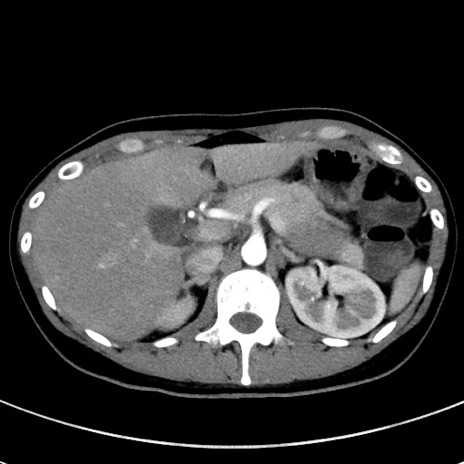

冠状断像

【症例】20歳代女性

【主訴】嘔吐、下腹部痛

【現病歴】昨日夕食後に嘔吐し下腹部痛が出現。本日になっても嘔吐持続し改善しないため来院。

【身体所見】意識清明、BT 37.2℃、BP 108/67mmHg、腹部:平坦、やや硬、下腹部正中から右にかけて圧痛あり、反跳痛軽度あり、tapping pain(+)。

【データ】WBC 13600、CRP 14.94